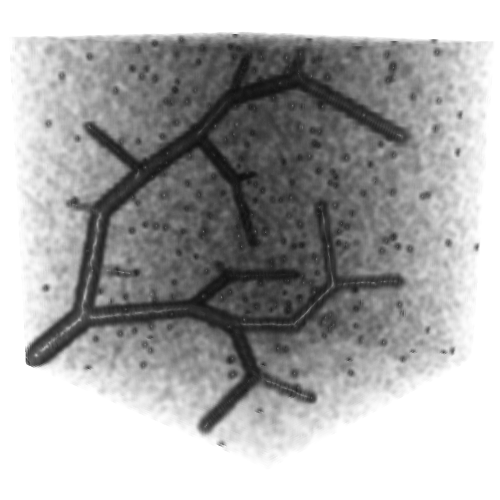

3.2 Connected Geodesic Paths as Vascular Tree

Representative examples of degraded synthetic images from SVT and the respective GT are shown in fig. 4 together with the connected graphs extracted by VTrails. Analogously, the same set of images are reported for the real images TOF and CTA in fig. 4. Qualitatively, the extracted set of connected geodesic paths shows remarkable matching with the provided GT in all cases. First, we verify the acyclic nature of the graph. We found no cycles, degenerate graphs and unconnected nodes, meaning that the extracted connected geodesic paths represent a connected geodesic tree. Precision and recall are then evaluated for the identified branches. Also, error distances are determined as the connected tree’s binary distance map evaluated at GT. Average errors () precision and recall are reported (meanSD) in table 1. Note that no pruning of any spurious branches is performed in the analysis.